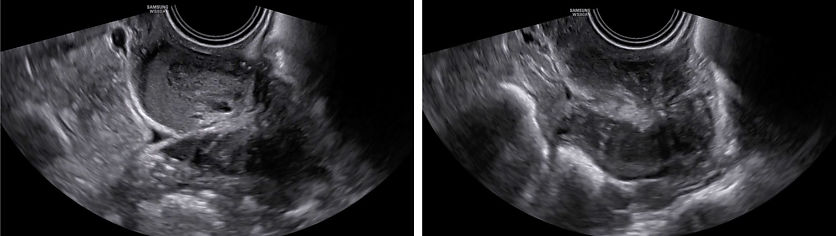

On ultrasound examination, typical endometriomas present as a cystic lesion with ground-glass echogenicity, with one to four locules and no solid components in a premenopausal patient (Figure 26). Of 713 histologically confirmed endometriomas in the International Ovarian Tumor Analysis (IOTA) studies, 65% were unilocular and 73% exhibited ground-glass echogenicity and 13% had low-level echogenicity.42 Atypical endometriomas are defined as unilocular-solid lesions with ground-glass echogenicity and a papillary projection, a color score of 1 or 2 and no vascularization inside the papillary projection (Figure 27).5 As per the recommendation of the IDEA consensus, the presence or absence of endometriomas should be described, as well as their number, size in three orthogonal planes and their ultrasound appearance according to International Ovarian Tumor Analysis (IOTA) terminology.43 Assessing vascularization by power Doppler may help in the differentiation between an endometrioma, a corpus luteum and a malignant lesion.44 A corpus luteum is characterized by strong circumferential blood flow (‘ring of fire’) and will generally resolve spontaneously after the menstrual cycle, unlike an endometrioma.

26

Ultrasound images of endometriomas with typical features of ground-glass echogenicity, up to four locules and no solid components.

27

Ultrasound images of atypical endometrioma, with the presence of a non-vascularized papillary projection.